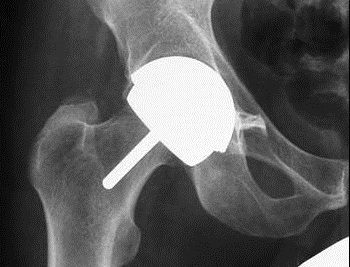

Künstlicher Hüftersatz: Gesicherte Versorgung für Menschen in Deutschland

Das Gesundheitssystem in Deutschland ist umfassend: Wenn ein Patient ein neues Hüftgelenk benötigt, wird ihm über seine Krankenversicherung der Zugang zu den neuesten ...